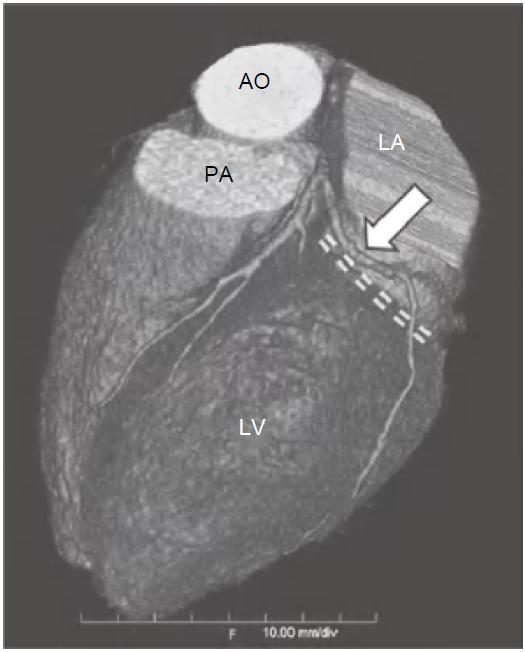

冠状动脉左主干(LMS)通常起源于左冠窦,位置低于RCA开口平面。通常在左心耳及肺动脉主干之间走行约1~2cm后分为LAD及左旋支(LCX),LAD在前室间沟内向下延伸至心尖(图13-1),LCX在左房室间沟(LAVG)内向后走行(图13-2)。

图13-2 左旋支(箭)起自左主干分叉处,并沿LAVG(虚线)走行,为左心室侧壁供血

AO.主动脉;PA.肺动脉;RV.右心室;LV.左心室